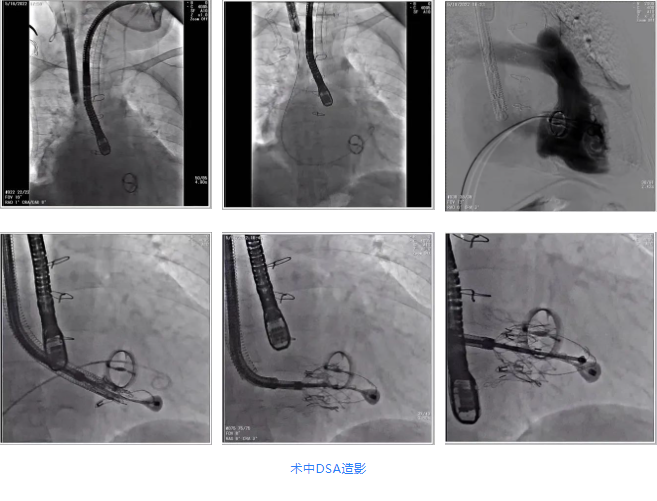

根據術前評估結果,郭應強教授團隊為患者量身定制了手術策略,決定使用LuX-Valve Plus經血管三尖瓣置換系統開展手術治療。手術在全麻下進行,采用經右側頸靜脈入路,在經食道超聲和DSA的指引下調整輸送器角度以達到正確位置,勾住前瓣后逐步釋放盤片,盤片打開后順利扎針,最終完成瓣膜植入,輸送器撤出。術后超聲提示人工三尖瓣同軸性良好,瓣架固定牢靠,無反流和瓣周漏,術后三尖瓣平均跨瓣壓差為1 mmHg。